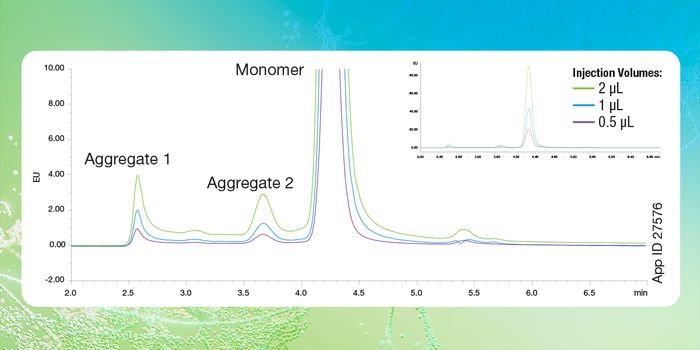

DEC 12, 2024Drug Discovery & DevelopmentAssessing immunogenicity is a cornerstone of modern drug development, especially for biologics and vaccines. Understandi ...